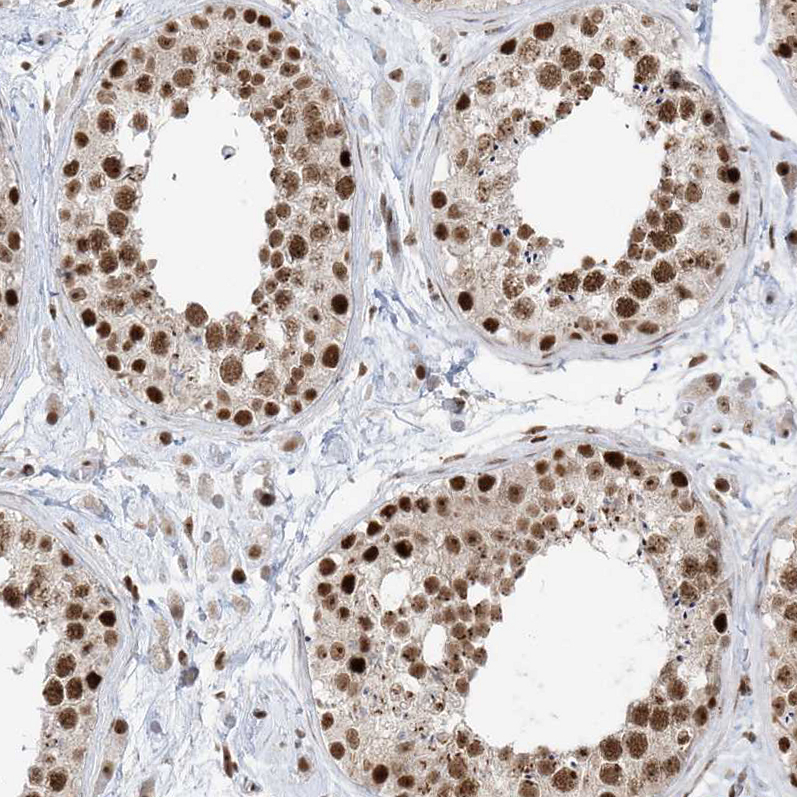

Immunohistochemical staining of human testis shows moderate nuclear positivity in cells in seminiferous ducts.